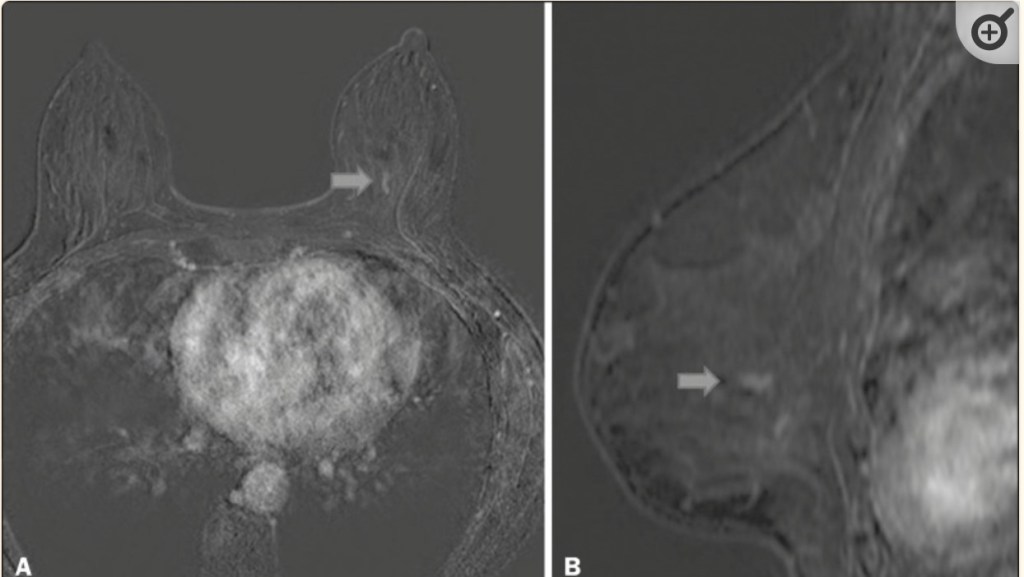

- The typical appearance of DCIS on MRI:

- Is non-mass enhancement

- Although mammography can be more sensitive than MRI for DCIS associated with calcifications:

- Uncalcified DCIS may be better visualized by MRI